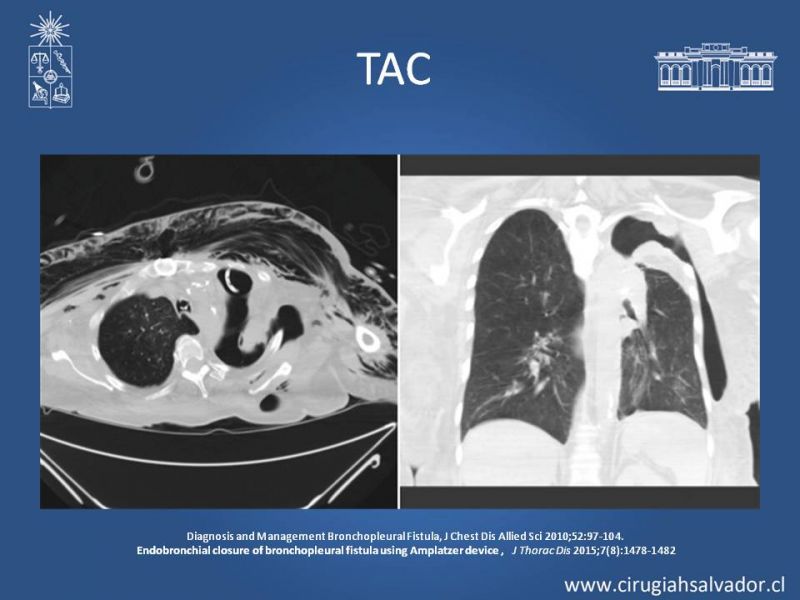

Fístula broncopleural

Cirugía Torácica

| Autor: Dr. Enrique Aguila Reyes